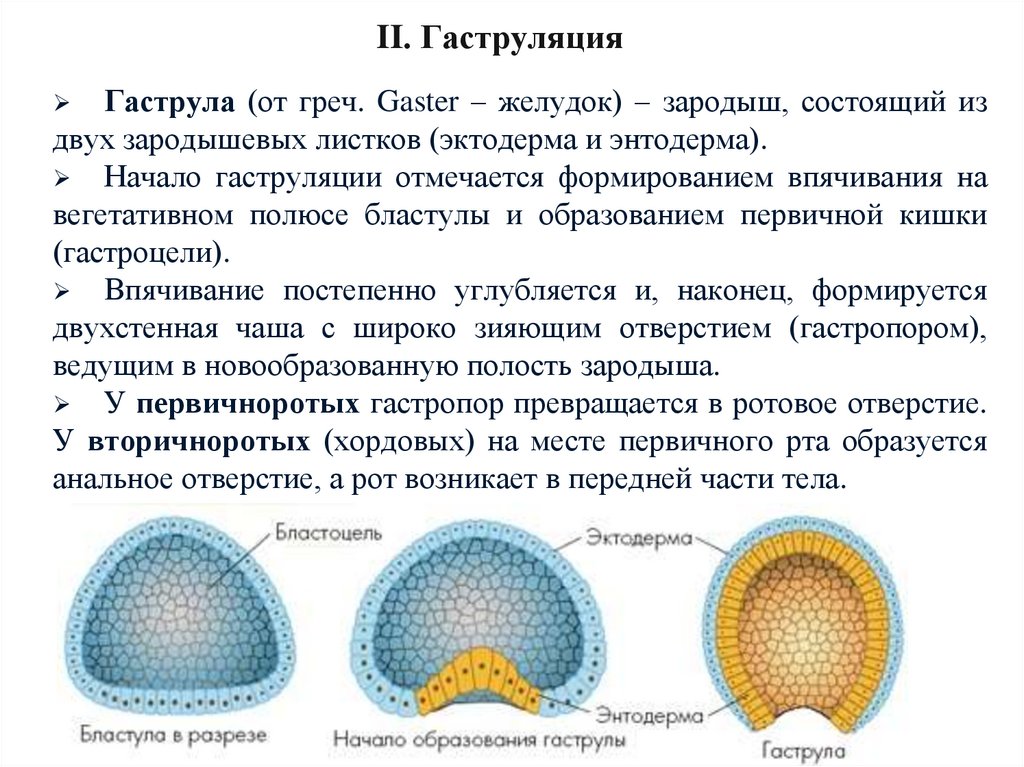

Эмбриональный период: Развитие эмбриона от зачатия до рождения